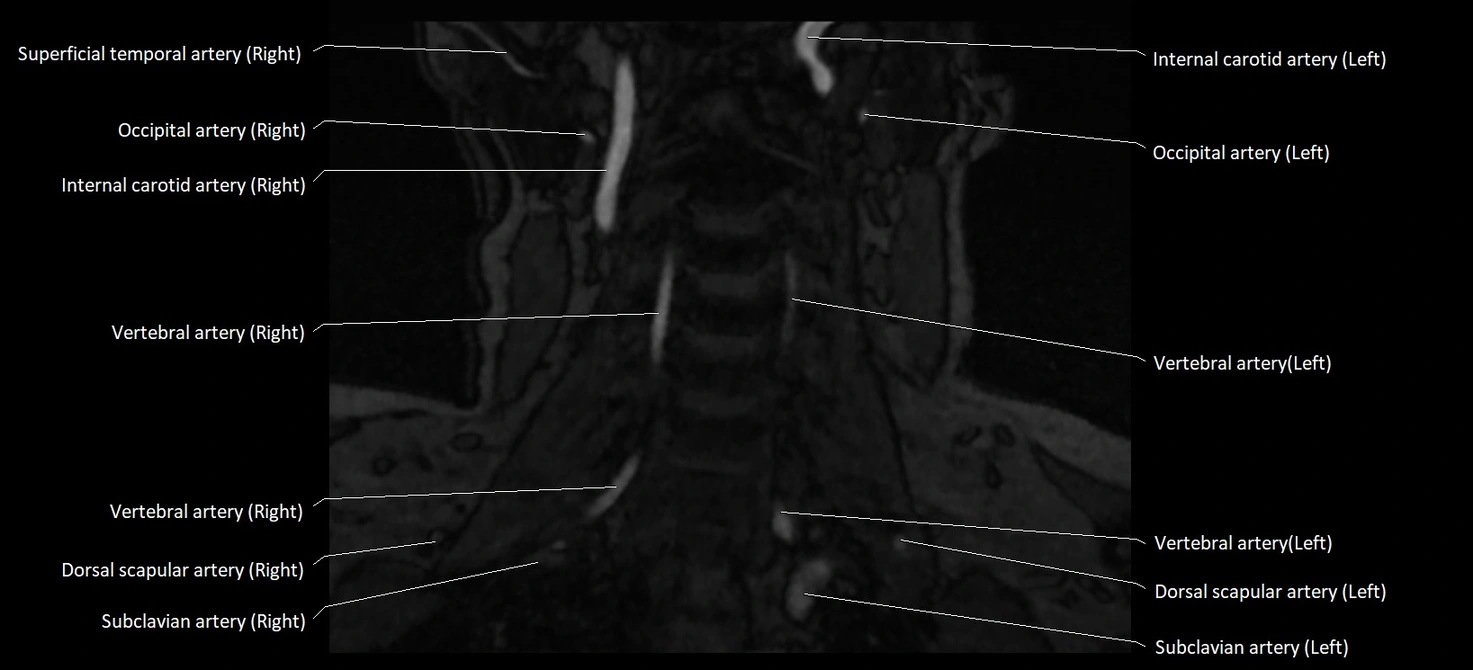

MRI images

image